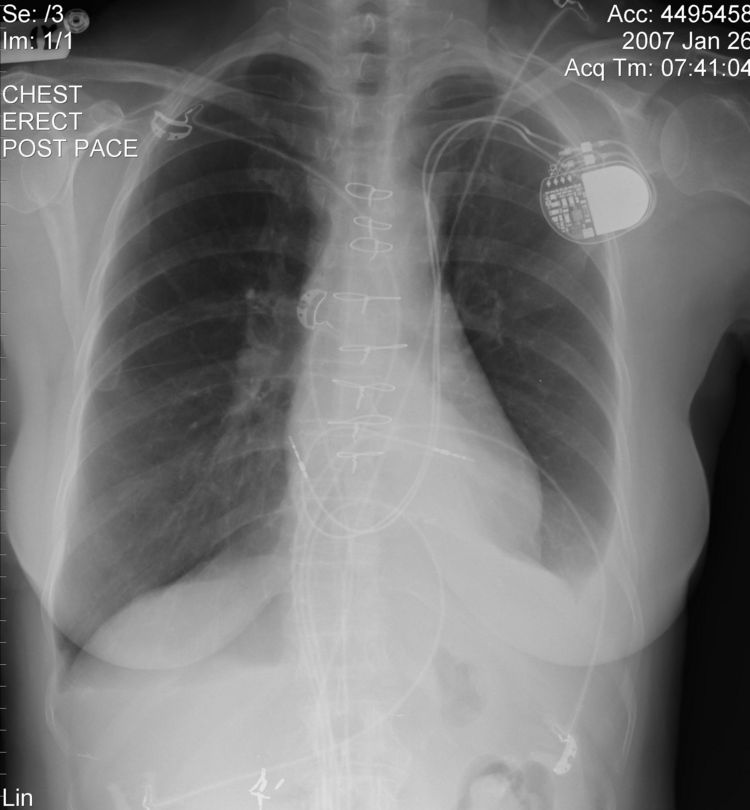

Persistent Left Superior Vena Cava

The above CXR show the atrial and ventricular pacemaker lead passing through a persistent left sided SVC.